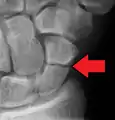

التشخيص

يتم عادة تشخيص كسر العظمة الزورقية بالتصوير بالأشعة السينية الجانبية, ولكن لا تظهر جميع الكسور في البداية ولذلك الناس اللذين يعانون من الم عند الضغط على منطقة السعوط يضعون جبيرة عصابة الإبهام من سبع إلى عشر أيام وحينها يتم اخذ مجموعة أخرى من صور الأشعة السينية.

وإذا كان هناك كسر شعري سيكون الشفاء واضحا, وحتى في ذلك الحين لن يكون كسر العظمة الزورقية واضحا, ويتم اخذ صورة بالأشعة المقطعية لتقيم العظمة الزورقية بوضوح أكبر, كما انه يفضل التصور بالرنين المغناطيسي إذا توفر عن التصوير بالأشعة المقطعية لأنه يمكن ان يعطي تشخيصا فوري. ويعد لا يظهر التصوير الملون طريقة فعالة لتشخيص الكسر الذي في صور الأشعة السينية.

معرض صور